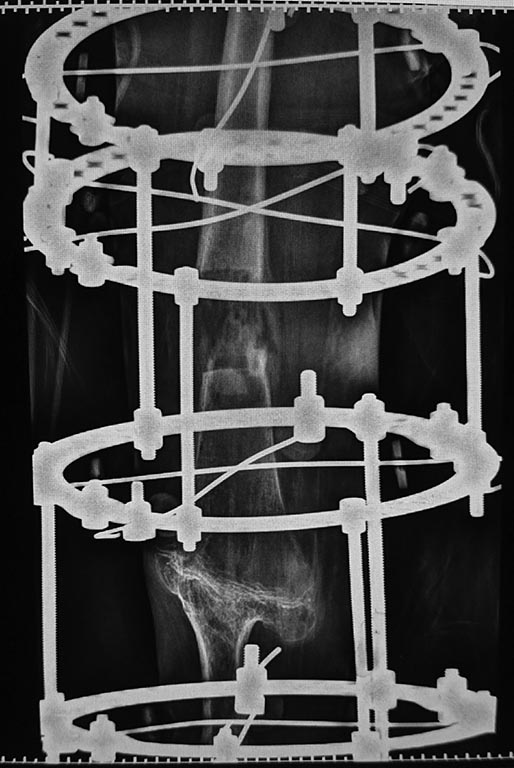

наложен аппарат бедро -голень и остеотомия бедра

Для более конкретных советов нужны фото и рентгенограммы.

Снимки

|

... да, дорогой, Ниязов Нияз, на бедре спицы могут натворить дел. Сориентируйтесь, пожалуйста, по прилагаемому атласу. Там все просто: выберите язык - кликните index.html - откроется сам атлас - кликните Атлас - выберите сегмент (ну, бедро, вестимо) - необходимые уровни.